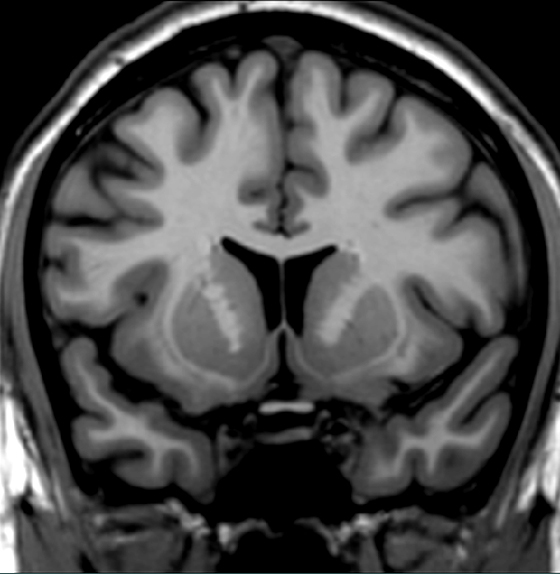

Identify one brain region where pressure from a pituitary tumor could produce a visual field defect.